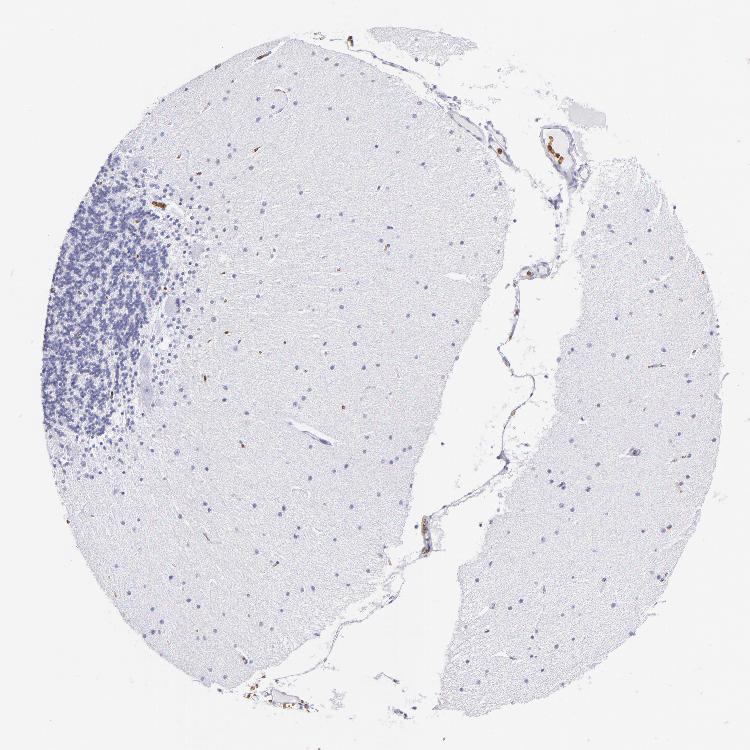

BRAIN CEREBELLUM Show tissue menu

CEREBELLUM - Expression summary

CEREBELLUM - Antibody stainingi

Antibody staining in the annotated cell types in the current human tissue is reported as not detected, low, medium, or high, based on conventional immunohistochemistry profiling in selected tissues. This score is based on the combination of the staining intensity and fraction of stained cells.

Each image is clickable and will lead to virtual microscopy that enables deeper exploration of all samples and also displays staining intensity scores, fraction scores and subcellular localization as well as patient and tissue information for each sample.

Antibody HPA014811Antibody CAB002658

Purkinje cells Not detectedNot detected

Cells in granular layer Not detectedNot detected

Cells in molecular layer Not detectedNot detected